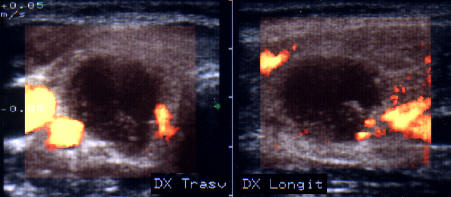

ecocolordoppler si powerdoppler- acelasi nodul

Vascularizatie interna, mai evidenta in powerdoppler.

Femeie 25 ani. Nodul unic in lobul stang, contur net, hipoecogen, respecta parenchimul din jur, neomogen, de 18x23x36 mm (7,5 cc).

Citoaspiratia cu ac subtire: nodul adenomatos.

Examen histologic postoperator: adenom trabecular fetal.

Acelasi caz. La doppler color - vascularizatie interna, mai evidenta in powerdoppler.